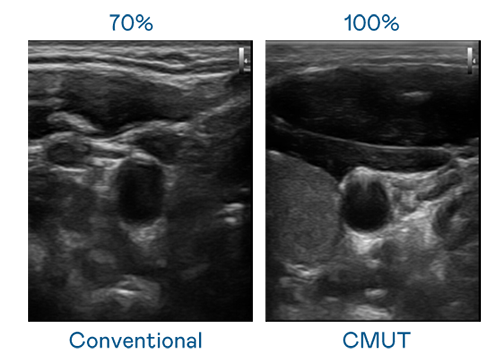

CMUT 技术是一种用电容式微机电元件来产生超音波讯号的技术。与传统 PZT 压电式技术相比,CMUT 频宽增加 30%,更宽频的超音波讯号让影像解析度大幅提升,是实现高影像品质医疗超音波扫描、促进精准医疗发展的关键技术。

大频宽带来超清晰影像

超音波影像的解析度高低,首先取决于探头能发出的讯号频宽。JJB竞技宝 CMUT 可提供高清晰的超音波讯号,提供高频宽、高灵敏度、影像纹理细节更高的超音波影像,协助医护人员缩短影像判读时间及利用精准的医疗影像进行诊断。